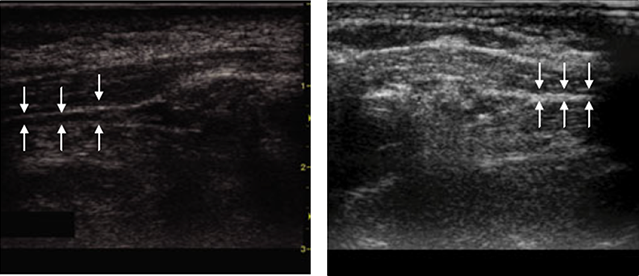

영상학적 검사로서 안면신경의 조영증강과 부종은 오래전부터 MRI에서 관찰되어 왔으며, 특히 Labyrinthine segment에서의 조영증강이 흔하게 보고된다. 그러나 조영증강 자체는 정상 변이에서도 나타날 수 있고, 예후와의 직접적 연관성에 대해서는 일관된 결과가 부족하며, 무엇보다 안면마비 환자에서 모두 MRI를 시행하기는 쉽지 않다. 최근에는 고해상도 초음파를 이용해 마비된 측의 유양돌기 하방에서 이하선 방향으로 주행하는 안면신경 직경을 측정하고 정상 측과 비교하는 연구들이 보고되고 있다. 일부 연구에서 마비측 신경 직경 증가가 불량 예후와 연관된다는 결과가 제시되었으나, 아직은 증례 수가 적어 향후 검증이 필요하다.

High-resolution ultrasound of the facial nerve in Bell’s palsy.

좌측: 우측 이하선 내 부종이 동반된 안면신경 (화살표)으로, 직경이 0.26 cm로 확장되어 있다.

우측: 반대측 정상 안면신경(화살표)으로, 직경은 0.11 cm이다.